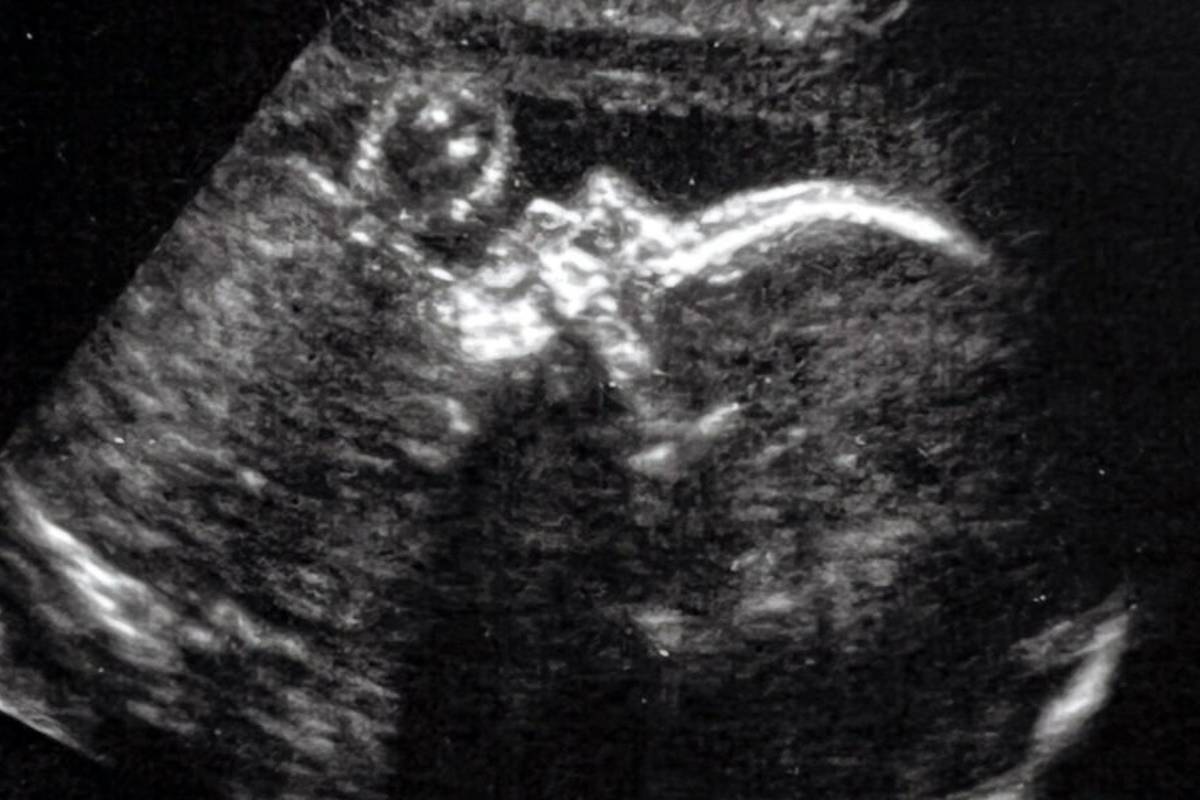

دیجیاتو نوشت؛ نوزادی که اکنون فقط 7 هفته سن دارد، به اولین فرد در جهان تبدیل شد که در دوران جنینی، تحت عمل جراحی مغز قرار می‌گیرد. در واقع گروهی از جراحان آمریکایی، موفق شده‌اند تا برای اولین بار با انجام عمل جراحی مغز روی یک جنین، یکی از ناهنجاری‌های مغزی پیش از تولد را درمان کنند.

جراحان «بیمارستان کودکان بوستون» و «بیمارستان Brigham and Women» با کمک اولتراسوند، از یک روش جراحی به نام «آمبولیزاسیون» (Embolization) برای درمان یک بیماری نادر قبل از تولد استفاده کردند. این بیماری که از آن به‌عنوان «ناهنجاری ورید جالینوس» یاد می‌شود، به خون اجازه می‌دهد تا پس از تولد کودک، به طرز خطرناکی در بخشی از مغز جریان پیدا کند.

بیمار این پرونده یک جنین 34 هفته‌ای بوده (دوره کامل حدود 40 هفته است) که برای اولین بار طی یک دوره سونوگرافی معمولی در هفته 30 خود، مشخص شده بود دارای ناهنجاری مغزی است. اورباخ در ادامه درباره وضعیت این نوزاد می‌گوید: